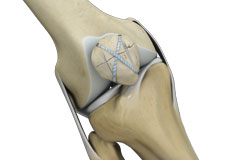

Patellofemoral Stabilisation

Patellofemoral stabilization is a broad term that refers to surgeries employed for stabilization (prevention of dislocation) of the patella for the treatment of patellofemoral instability.

Patellofemoral Realignment

Patellofemoral realignment is a surgical procedure performed to treat symptomatic patellofemoral instability that does not respond to nonsurgical treatment measures.